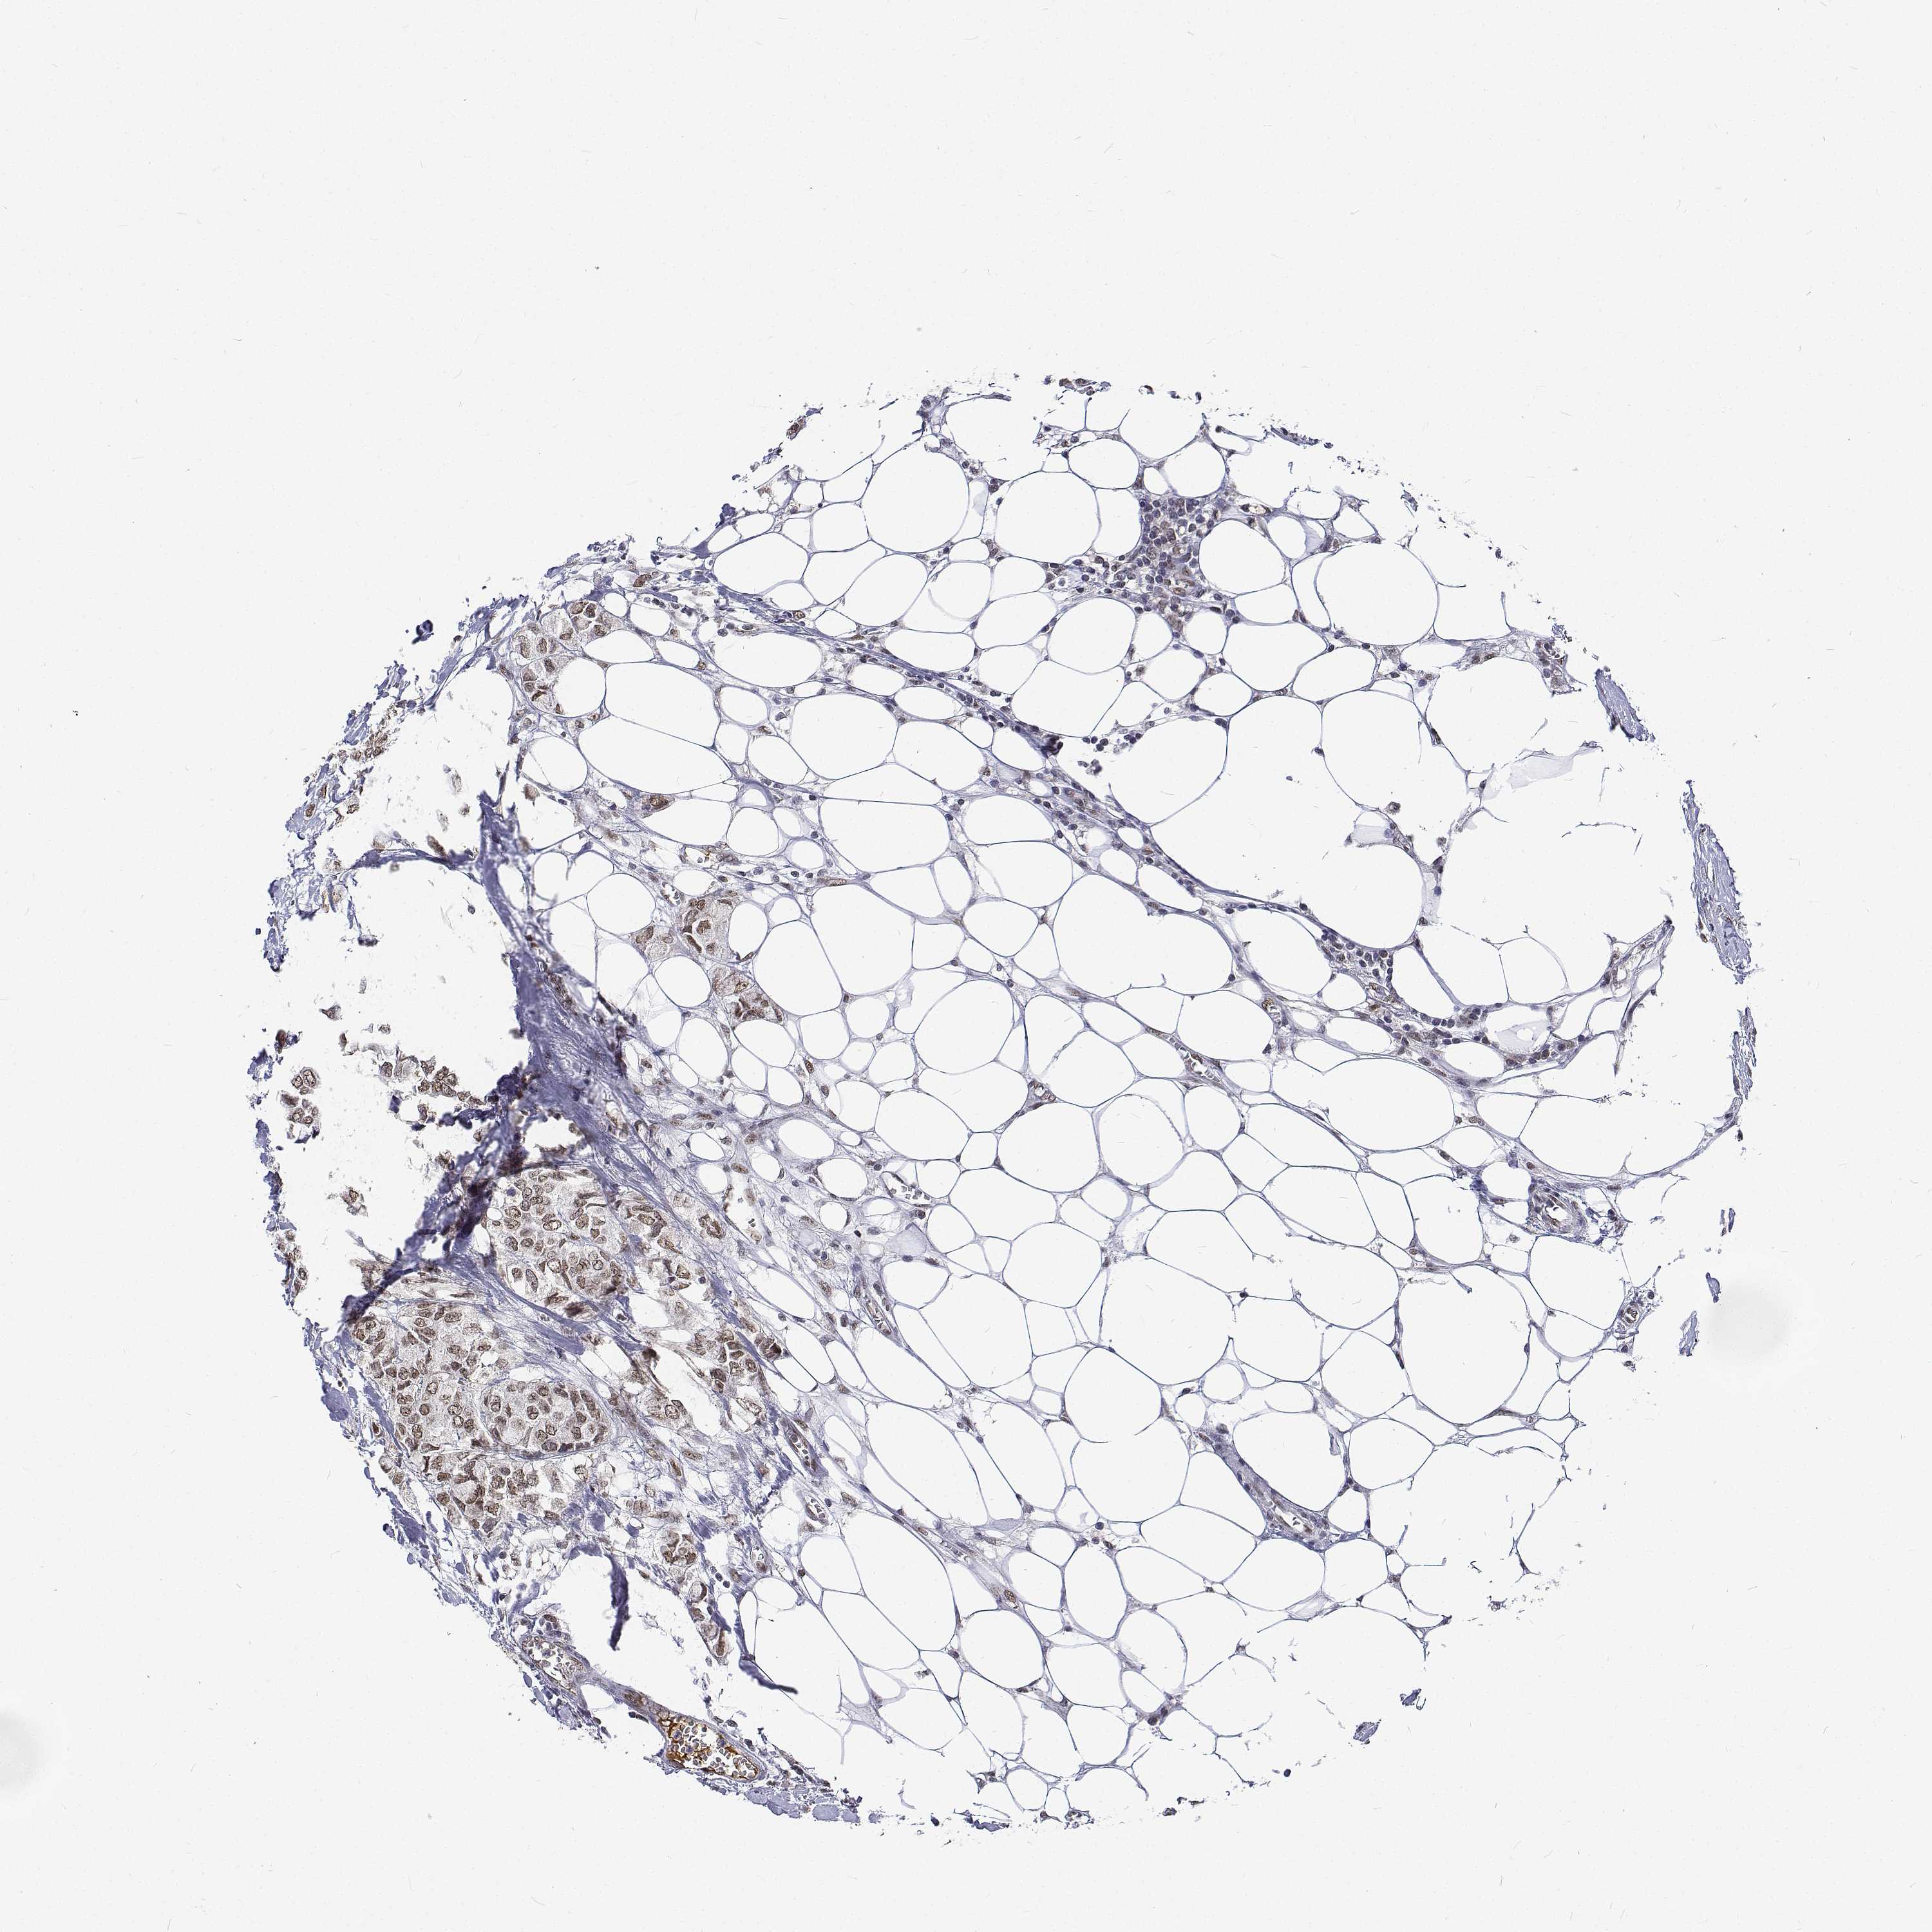

CANCER BREAST CANCER Show tissue menu

BRCA TCGA BRCA VALIDATION PROTEIN EXPRESSION